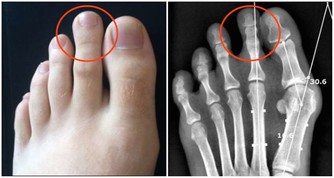

3、舌頭上有很多裂溝

除了老年人,正常情況下,人的舌頭不會出現太多裂溝。但脾胃虛弱的人則容易出現很多裂溝。這是因為脾胃虛弱者,體內水濕滯留,容易造成舌頭浮腫,促使舌頭與牙齒互相擠壓,從而使患者舌頭出現裂溝。